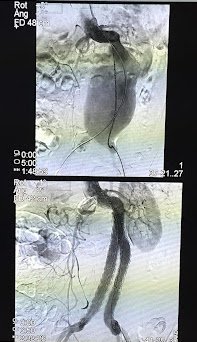

Pre-treatment: Bilateral iliac vein occlusion

Pre-treatment

Bilateral iliac vein occlusion associated with pelvic congestion syndrome.